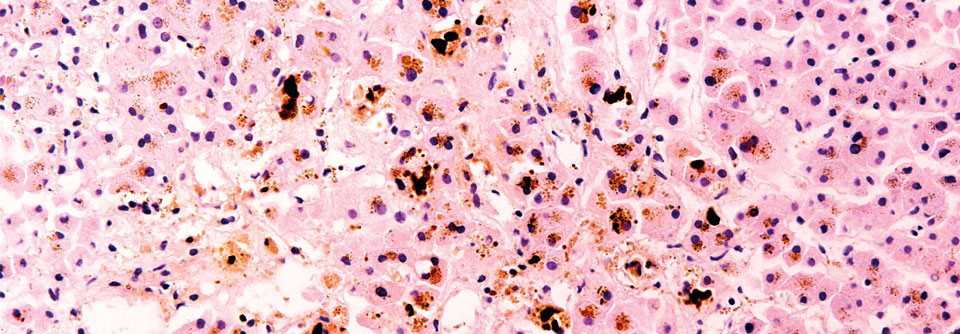

Bei Arthropathie auch an die angeborene Hämochromatose denken

Oft sind es Gelenkbeschwerden, die den Patienten wegen einer hereditären Hämochromatose zum Arzt führen. Das ist kaum verwunderlich, fallen dem Betroffenen diese Störungen im Alltag doch wesentlich eher auf als etwa eine Leberschädigung.

Eine Arthropathie liegt bei 24–81 % der Personen mit der vererbten Eisenspeicherkrankheit vor, schreibt Dr. Axel Braner von der Rheumatologischen Ambulanz am Frankfurter Universitätsklinikum. Schon dieser breite Bereich der in der Literatur genannten Zahlen deutet an, dass das Spektrum klinischer Gelenkmanifestationen als Folge der Stoffwechselstörung breit ist und dass keine einheitlichen Kriterien für die Beurteilung der Gelenkmanifestationen…